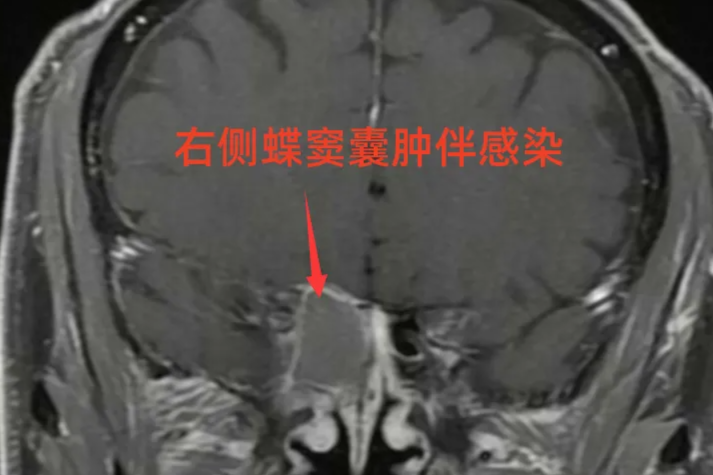

眼睛模糊还头痛?别总怪手机!原因藏在鼻腔里……